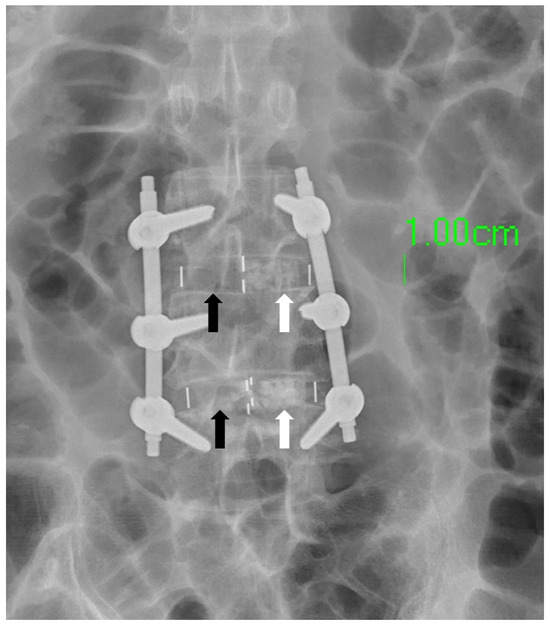

- In this study, we used two methods to place bone substitute into cages. The SG cage group (side hole for grafting group) involved using a cage with a side hole to fill it with bone substitute after implantation (Figure 2a). The FP cage group (finger-packing group) involved filling the cage with bone substitute before implantation using finger packing (Figure 2b).

- SG cage group: This study employed a cage with filling side holes (a specially designed innovative cage with “side hole for grafting”). Firstly, a soft-material printed intervertebral disc was placed into a 3D-printed spinal model, followed by the implantation of the specially designed cage into the soft-material printed intervertebral disc. Bone substitute was then filled into the cage through the side holes until it was completely filled. Subsequently, the intervertebral disc substitute, cage, and bone substitute were removed together and weighed using a high-precision scale (Figure 2c). This step was repeated 10 times for each group based on the different heights of the cage.

- FP cage group: Traditional methods were used in this study. Firstly, a soft 3D-printed intervertebral disc was placed into a 3D-printed spine model. Next, bone substitute was packed into the interior space of the 3D-printed cage using the finger-packing technique. An inserter was then employed to connect the 3D-printed cage, and a hammer was used to aid the implantation of the 3D-printed cage into the soft intervertebral disc within the spine model. After implantation, the weight of the 3D-printed intervertebral disc, cage, and internal bone substitute was measured using a high-precision scale and recorded. This step was repeated 10 times for each group based on the height of the cage.